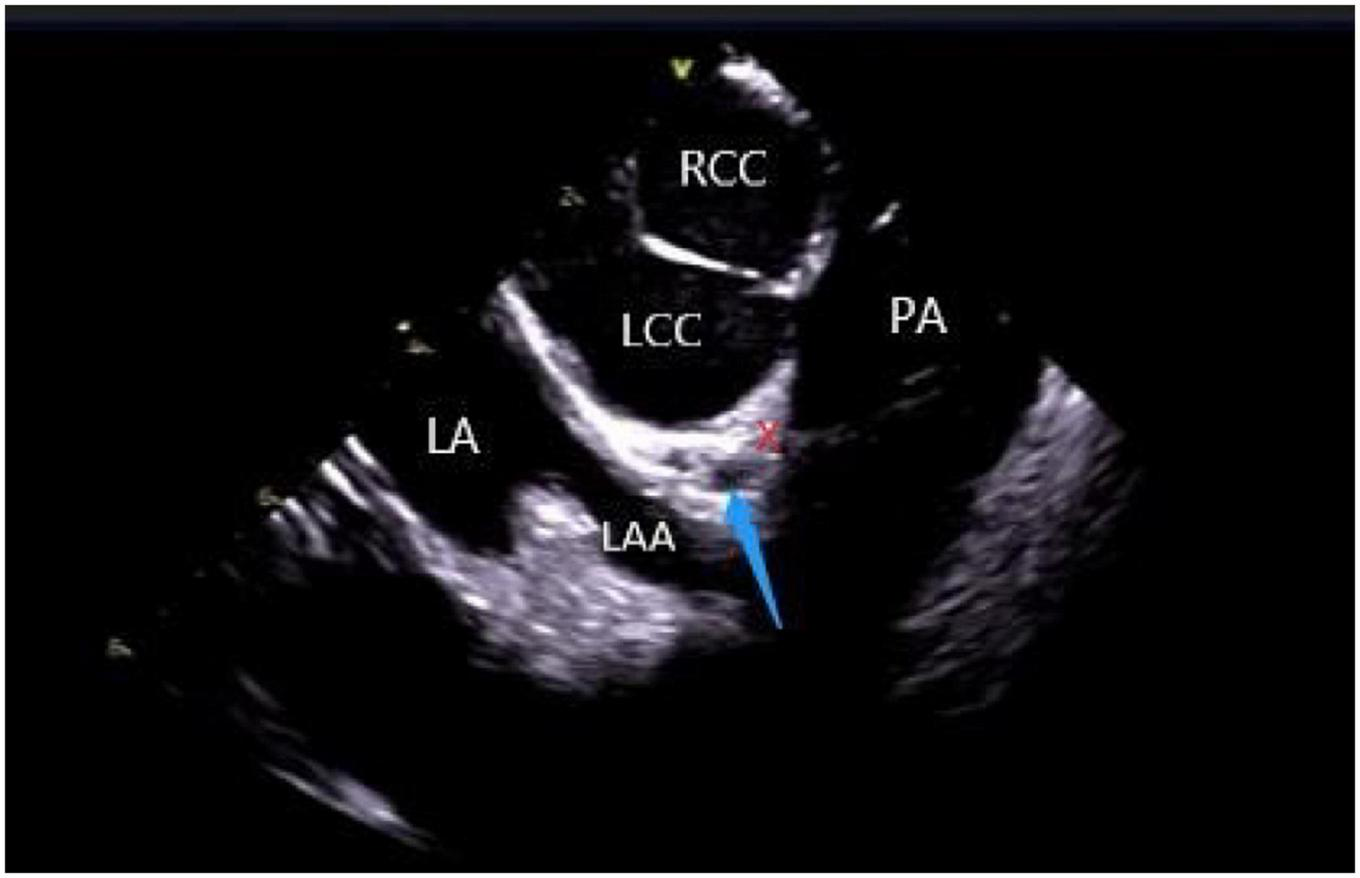

The left ventricular summit (LVS) is the triangular region at the most superior part of the LV epicardial surface consisting of the left circumflex coronary artery, the left anterior descending artery, and an approximate line from the first septal coronary artery laterally to the left AV groove. As the LVS region is bisected by the great cardiac vein (GCV), an area superior to it is inaccessible to catheter ablation due to the proximity of the coronary arteries and overlying epicardial fat (26). It is suggested that PVCs in this area sometimes require “anatomical ablation,” and the successful target may not be the earliest source of excitement (27). In the traditional 3D model, the presence of an unexplored area might result in incomplete model construction and ablation failure. Hence, coronary angiography or cardiac venography is usually used to guide the localization, while the distance between the ablation catheter and the epicardial coronary artery exceeding 0.5 cm is considered safe to avoid vascular damage (28). However, some studies have revealed that catheter ablation of adjacent structures like the aortic valve and RVOT under ICE-assisted imaging is highly effective (29) (Figure 6). Furthermore, although the selective resolution of the ICE prohibits the viewing of the small veins, the operator can successfully perform ablation in the branch without venography. Rivera et al. reported successful zero-ray ablation procedures in 26 cases of PVC/VT originating from the LVS region, with an immediate success rate of 84% due to the guidance of an ICE-guided 3D electroanatomical mapping system without any serious complications (30).

FIGURE 6

ICE view of the aortic root and pulmonary artery at the left ventricular summit region, viewed from the right ventricular outflow tract. At the center, a short axe of the left main coronary artery (LMCA) (blue arrow) surrounded by a thick layer of adipose tissue (LVS). RCC, right coronary cusp; LCC, left coronary cusp; LA, left atrial; LAA, left atrial appendage; PA, pulmonary artery; The LVS is marked with an X.